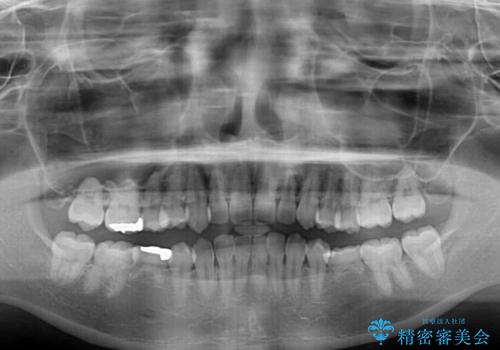

- 犬歯のクロスバイトを気にして来院された患者様です。

マウスピース矯正とワイヤー矯正の両方を提案しましたが、インビザラインの自己管理が煩わしいとのことで、ワイヤー装置による矯正治療を行うこととしました。

犬歯は歯根が太くて長いため、クロスバイトを改善するのは大変であることが多いですが、比較的スムーズに改善することができました。